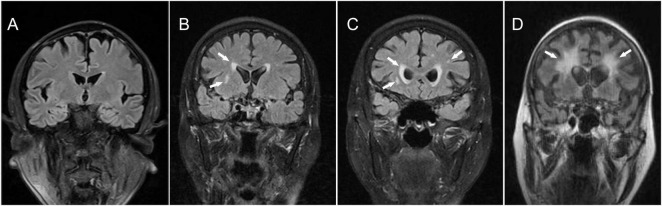

Background: Chronic cerebral hypoperfusion (CCH) is a key contributor to vascular cognitive impairment (VCI). Patients with CCH frequently exhibit white matter hyperintensities (WMH) on MRI. This study investigated the expression and clinical relevance of megakaryocyte-associated tyrosine kinase (MATK) in CCH patients with WMH.

Methods: We recruited 42 anterior circulation stenosis patients with CCH and WMH (CCH-WMH group) and 45 age-matched healthy controls. MATK mRNA expression in peripheral blood mononuclear cells (PBMCs) was quantified using qPCR. WMH severity was graded using the Fazekas scale. Correlations between MATK expression and imaging/clinical parameters were analyzed using Pearson's correlation and logistic regression. Diagnostic performance was assessed via ROC analysis.

背景:慢性脑灌注不足(CCH)是血管性认知障碍(VCI)的重要诱因。CCH患者在MRI上经常表现为白质高信号(WMH)。本研究探讨巨核细胞相关酪氨酸激酶(MATK)在CCH合并WMH患者中的表达及其临床意义。方法:我们招募42例CCH和WMH前循环狭窄患者(CCH-WMH组)和45例年龄匹配的健康对照。采用qPCR方法定量外周血单个核细胞(PBMCs)中MATK mRNA的表达。采用Fazekas量表对WMH严重程度进行分级。采用Pearson相关和logistic回归分析MATK表达与影像学/临床参数的相关性。通过ROC分析评估诊断表现。结果:CCH-WMH组巨核细胞相关酪氨酸激酶表达明显下调(1.20±0.99∶1.84±0.87;P < 0.01)。MATK水平与Fazekas评分呈显著负相关(R2 = 0.3405, P < 0.001)。多因素回归发现MATK与WMH独立相关(aOR = 0.492; 95% CI: 0.262-0.923; P = 0.027)。ROC分析显示WMH的诊断准确度中等(AUC = 0.743; 95% CI: 0.637-0.849)。结论:外周MATK表达降低与CCH患者WMH严重程度相关,可能是一种潜在的诊断生物标志物。